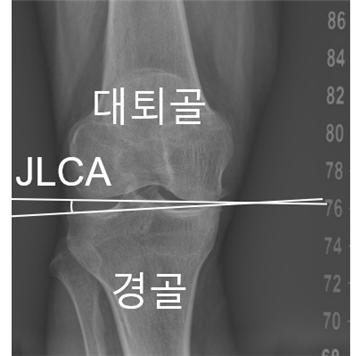

연구팀은 무릎 관절을 이루는 대퇴골과 경골 사이의 관절선이 벌어진 정도인 ‘관절선 수렴각(JLCA)’이 이러한 가속 진행을 예측하는 공통 지표임을 밝혀냈다. 초기에 측정된 JLCA가 1° 커질 때마다 O자형 환자에서 12.9%, X자형 환자에서 19.4%씩 가속 진행 위험이 증가했다. 특히 O자형 환자의 경우 관절염 중증도가 높을수록 가속 진행 위험이 증가했으며, 중등도 이상(Grade III, IV) 단계에서는 정상군(Grade 0) 대비 약 4~5배 높은 것으로 나타났다.